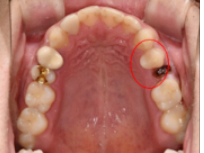

임플란트 1차 치료 후

2021.07.23 / 2021.08.02 (1차,2차 후)

환자분은 상담 1주일 후 내원을 해주셨습니다. 발치와 함께 임플란트 1차 치료가 진행되었습니다.

임플란트 뿌리가 되어줄 '인공치근'을 심었습니다.(1차 치료) 그 후 일주일 뒤 보철과 인근치근을 연결해 주는 지대주를 식립하셨습니다. (2차 치료)

무사히 1차, 2차 치료를 마치셨고, 3개월 뒤 최종 보철물 부착을 위해 내원하시기로 하셨습니다.